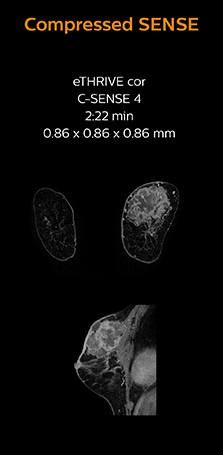

“In breast scanning, high resolution is important to help me identify very small mammary lesions, so, we need high spatial resolution in 2D T1- and T2-weighted images, as well as a short scan time. Compressed SENSE has allowed us to increase spatial resolution, which benefits our diagnostic confidence.”

Dr. Koyama says that he used to believe that high resolution MRI at 1.5T required long scan times, and SNR was low. “With Compressed SENSE, however, it is possible to acquire high quality images, even with higher Compressed SENSE factors, so in a quite short time.”

Dr. Koyama says that a C-SENSE factor of 4.0 was chosen to increase their spatial resolution in 3D dynamic breast scanning. “In addition to a high temporal resolution, we also require high spatial resolution, which helps us to see details of the internal structure of the lesion and to see lesions separately from normal anatomic structures. We can also see if a lesion extends into adjacent organs and anatomic structures.”

This patient underwent MRI on Ingenia 1.5T with Compressed SENSE. Compressed SENSE was used to reduce the scan time in order to decrease the time that the patient may experience discomfort and pain, both of which may lead to patient motion. The 3D BreastVIEW and 3D high resolution mDIXON images – both mDIXON contrasts are acquired in the same exam – show high quality images even with the shorter scan time. The spatial resolution of the dynamic scan with Compressed SENSE is higher than in the previous protocol (not shown) which allows for better visualization of the lesion with respect to the muscles of the thoracic wall and better delineation of small structures.

For breast imaging, a fast, high resolution scan can be important for a female patient having to lie in an uncomfortable, face-down position in the scanner. Compressed SENSE also helps us to obtain higher1 quality images using 3D BreastVIEW and 3D high resolution mDIXON sequences in the same examination time as in our previous exam protocol.